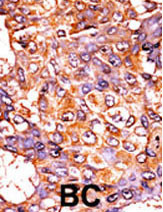

Formalin-fixed and paraffin-embedded human cancer tissue reacted with the primary antibody, which was peroxidase-conjugated to the secondary antibody, followed by AEC staining. This data demonstrates the use of this antibody for immunohistochemistry; clinical relevance has not been evaluated. BC = breast carcinoma; HC = hepatocarcinoma. |